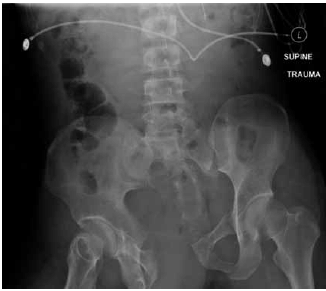

Mulher, 29 anos, sofreu queda de moto, evoluindo com perda de consciência e instabilidade hemodinâmica. Foi submetida à intubação orotraqueal e o e-FAST foi negativo em todos os pontos estudados. Realizou a radiografia demonstrada na imagem.

De acordo com os dados apresentados, assinale a alternativa correta.